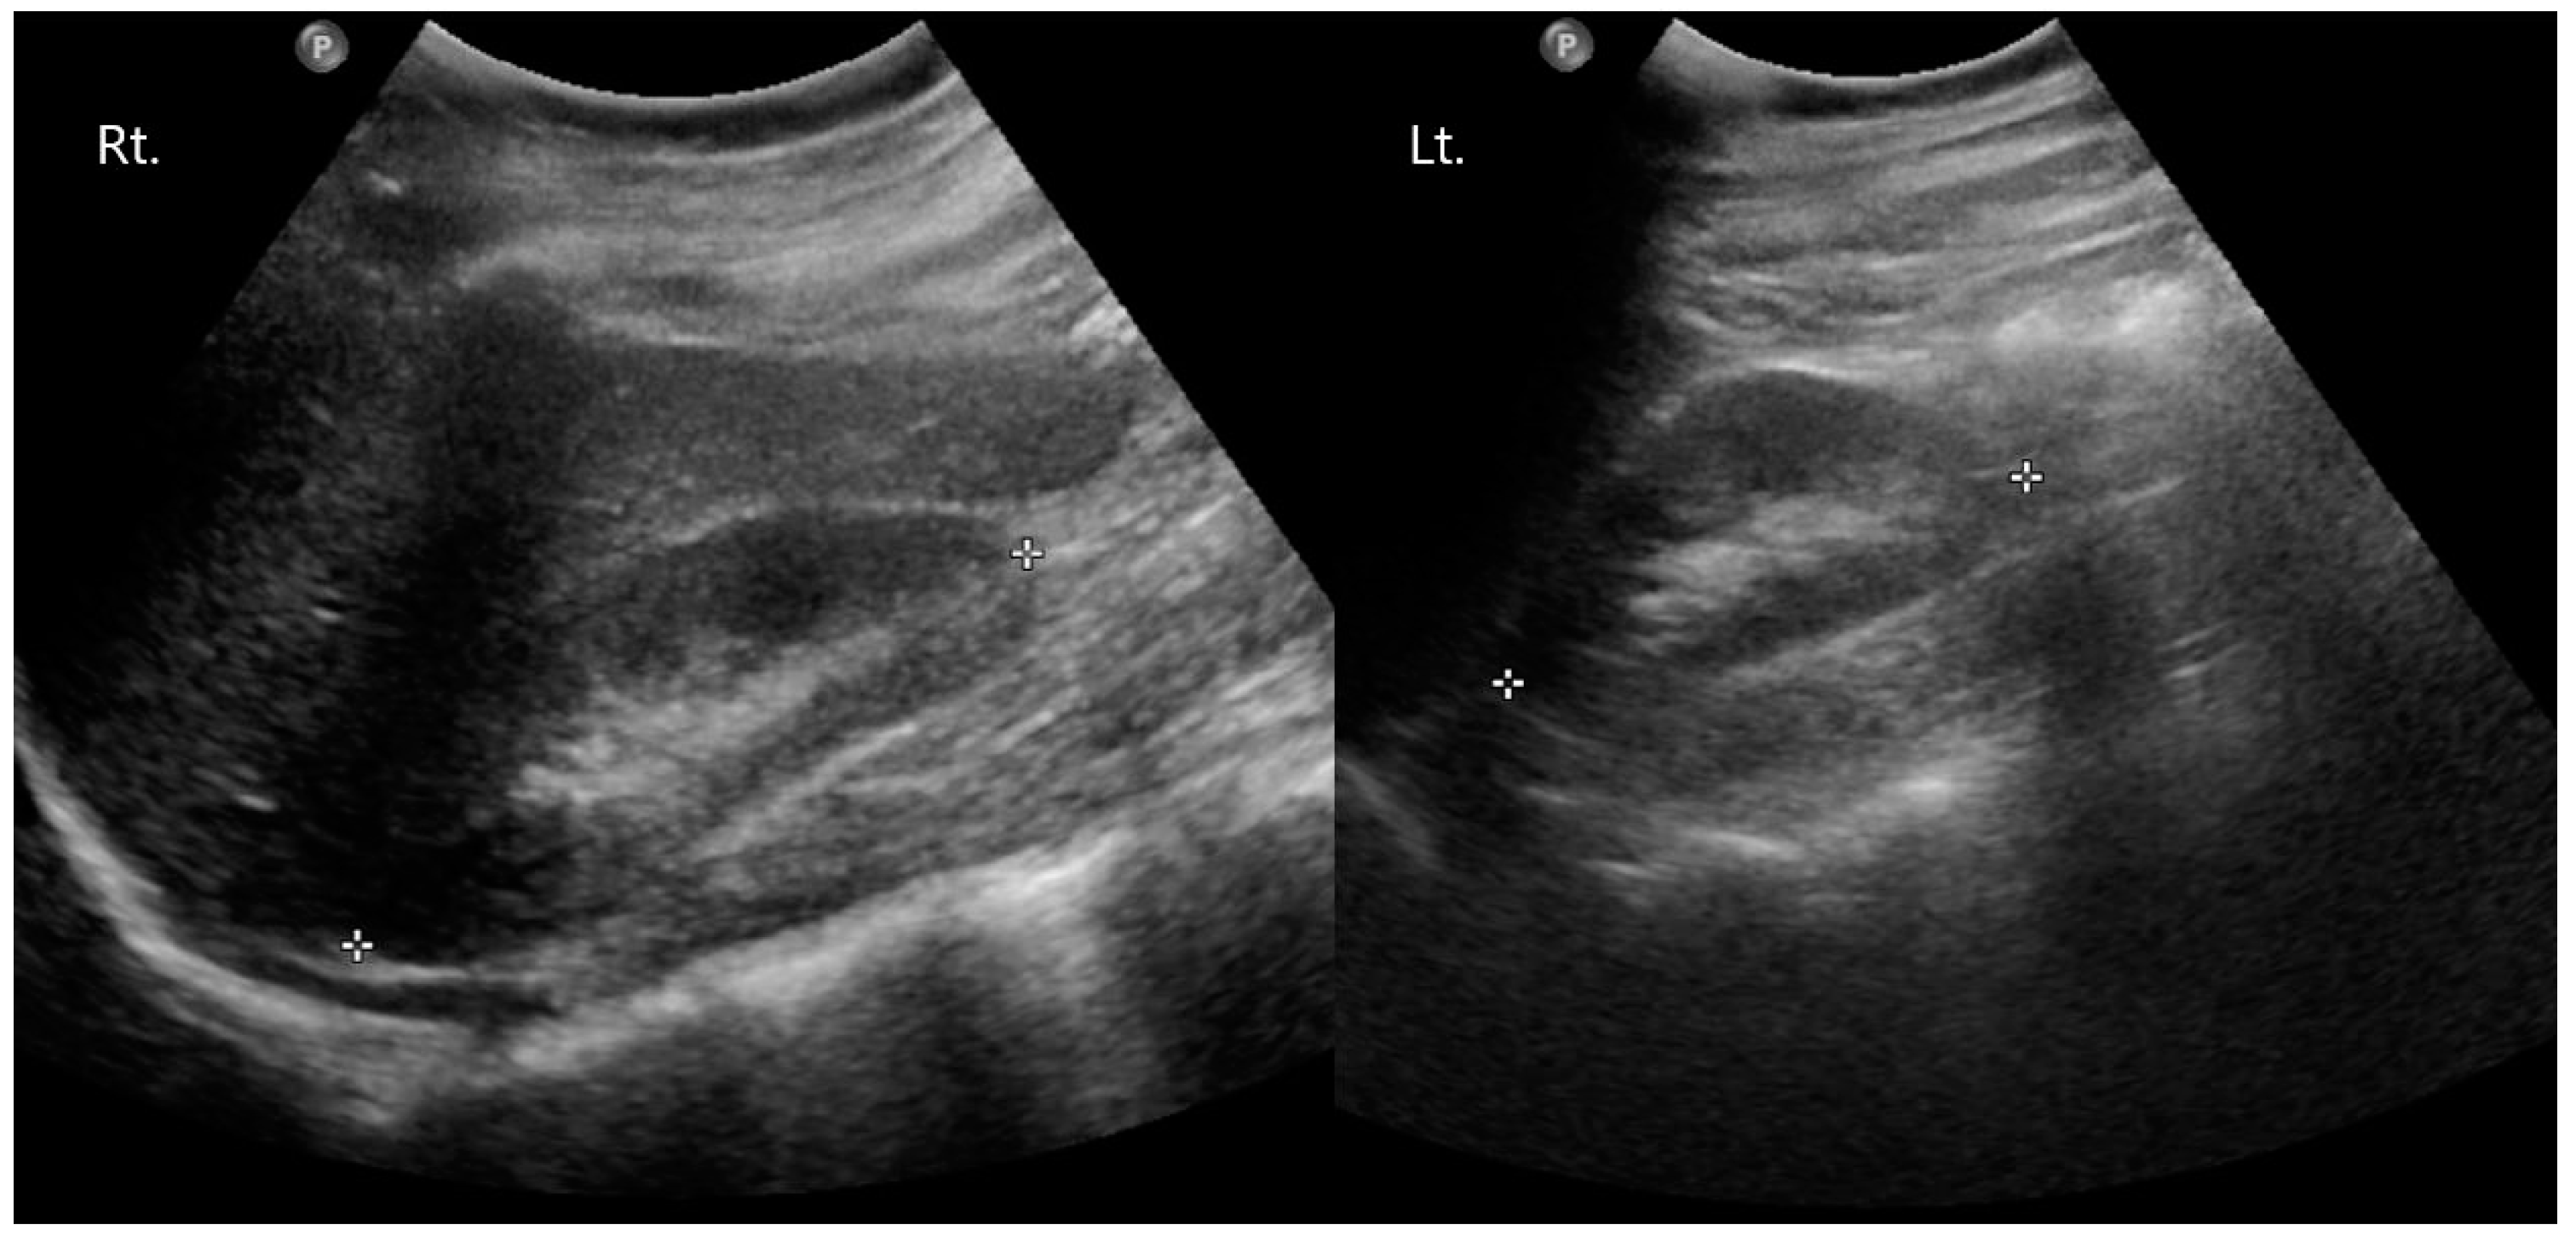

2. Case Presentation

2.1. Preoperative Evaluation